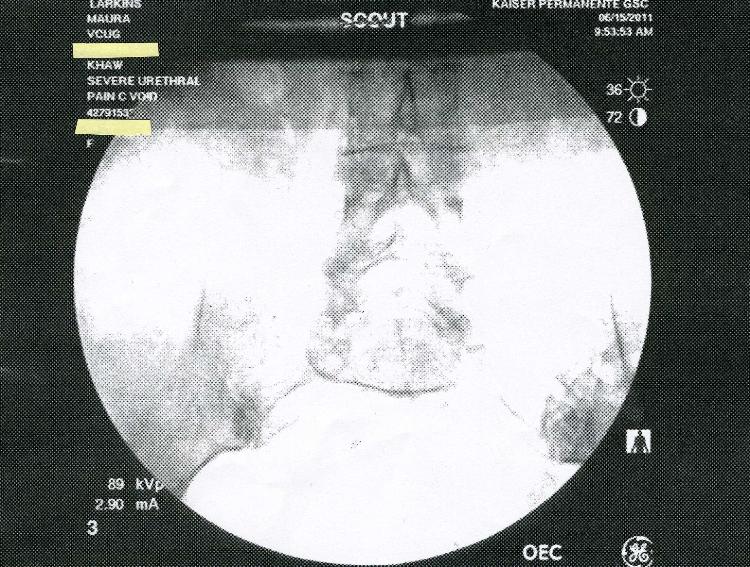

In July 2011 Kaiser Permanente in San Diego claimed that a large series of

X-rays done at the brand new Garfiled Specialty Center was not preserved on

film or saved electronically.  Kaiser claimed that only five images were

saved-on thermal paper! Below are the five images.  Incredibly, two of the

saved images are previews, or "scout" x-rays.  Why would these be printed

out?  They were not medically useful.  Answer: The truth is that all the images

were saved digitally, and Kaiser concealed them to cover-up an incorrect

diagnosis.